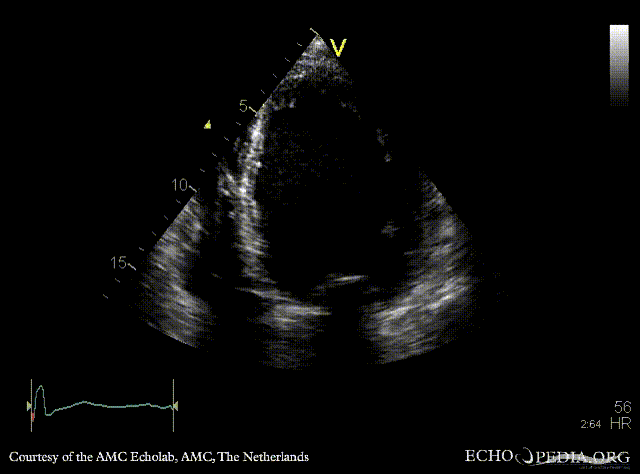

| Courtesy of: AMC Echolab, AMC, The Netherlands | |

| A2CH | A3CH |